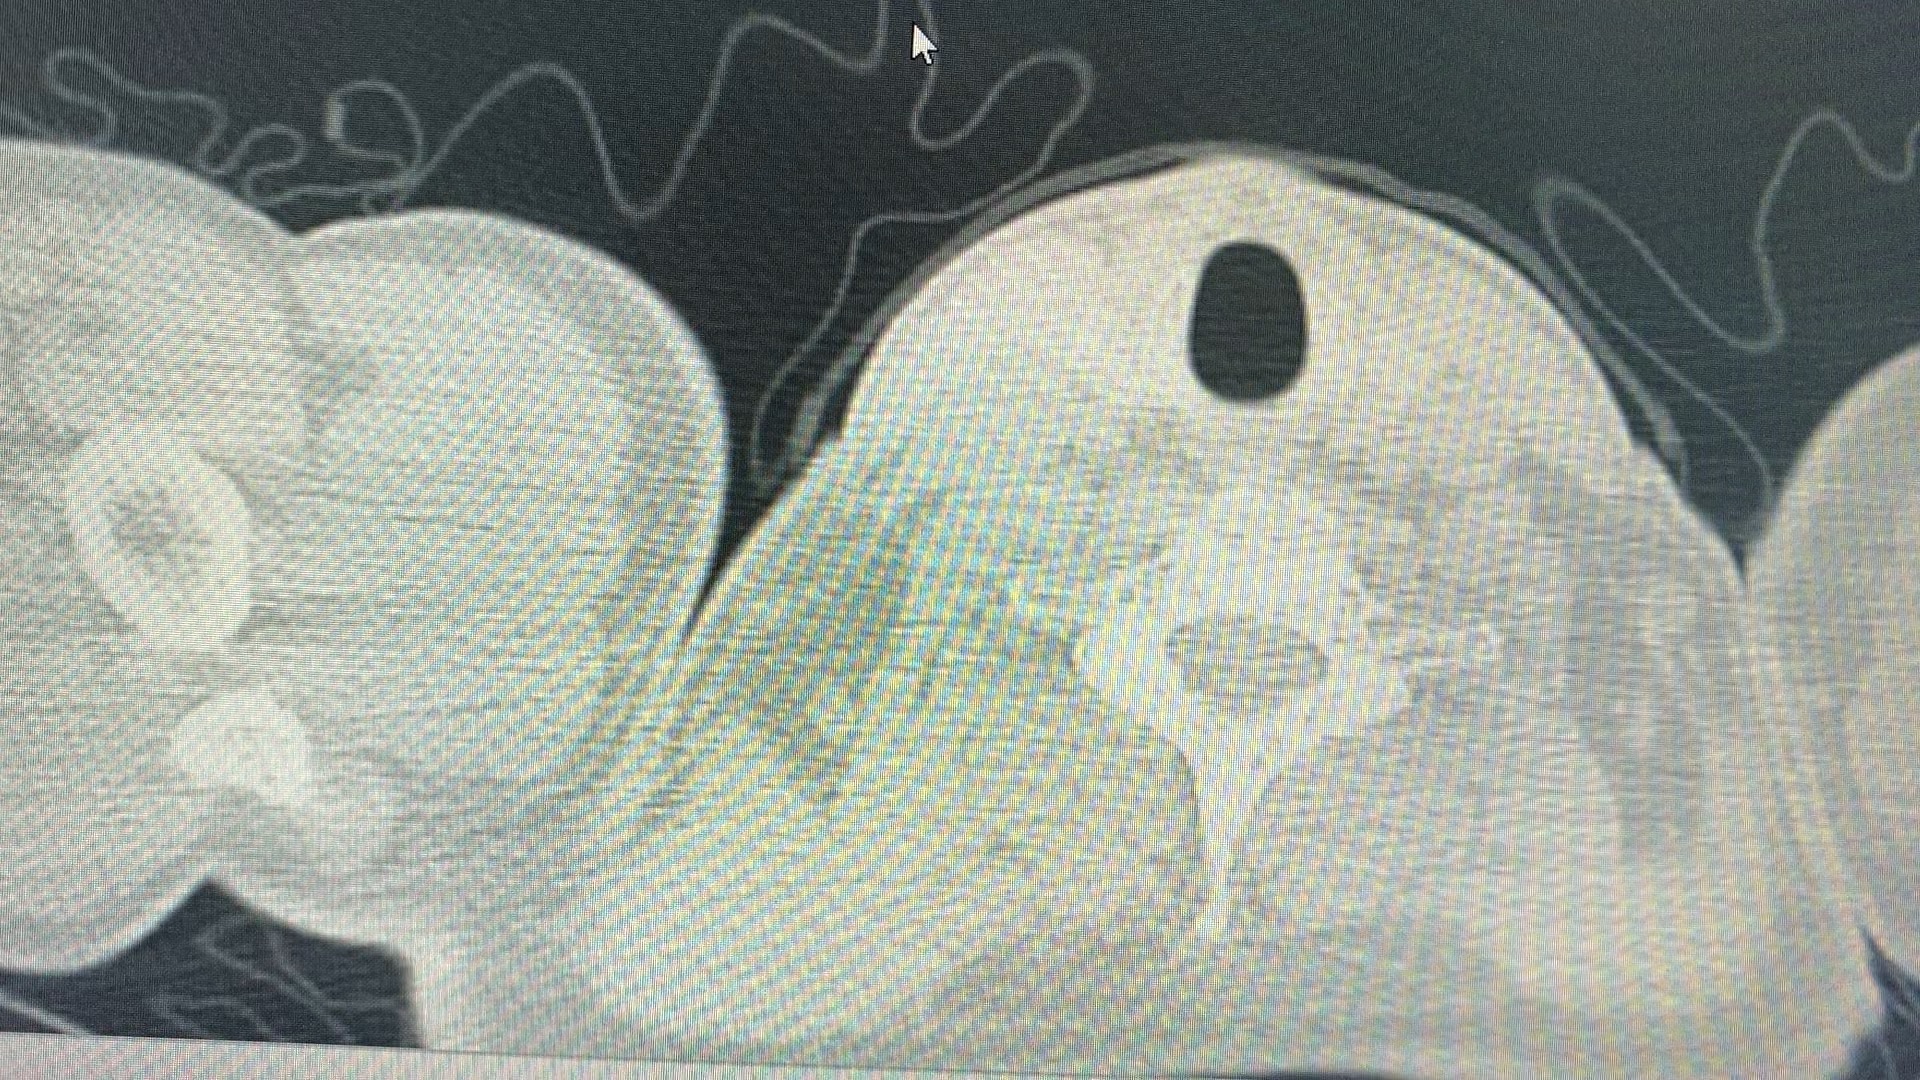

患者男,55岁,发现肺部结节6年。无特殊不适。既往无特殊病史。

2019年

2025.10.30